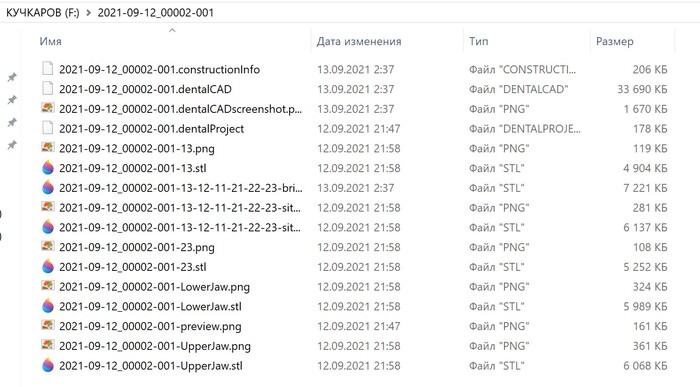

На флэшке оказались снимки чьей-то челюсти из стоматологии, датированные 2021 годом. И тут паззл сложился... Мы арендуем квартиру с ноября 2021 года, то есть флэшка уже была в стиралке и принадлежит предыдущему арендатору. Стираем мы в среднем 2 раза в неделю, то есть прошло около 200 циклов стирки и флэшка жива!!! В общем, kingston, я удивлен. Господин Кучкаров, если случайно читаешь это, заезжай за флэшкой:)))))